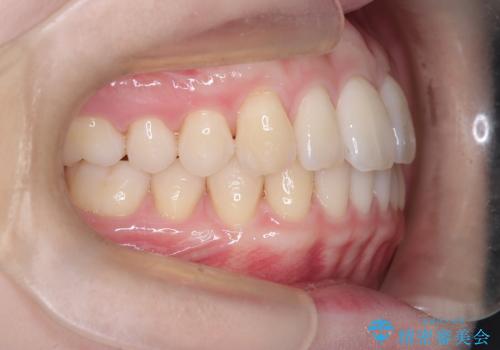

- 左上2の反対咬合(交叉咬合)をインビザラインを用いて治療しました。反対咬合は、歯列の不正咬合の一つであり、上の歯が下の歯よりも内側に位置する状態です。反対咬合は咀嚼や発音に影響を与えることがあります。

左上2の反対咬合をインビザラインで治療する際に、IPR(Interproximal Reduction)を行いました。 IPRとは、隣接する歯の間のエナメル質をわずかに削る手法で、歯の幅を減少させることによって歯列を整える技術です。